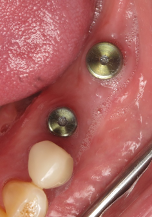

A healthy 60-year-old female presented for an emergency evaluation because she was experiencing pain associated with tooth No. 20. It was mobile, malposed, and given a diagnosis of irreversible pulpitis. In addition, teeth Nos. 19 and 21 had been missing for more than 5 years. After the evaluation, a discussion revealed that the patient desired implant reconstruction of the lower left quadrant. During this initial visit, a CBCT scan was obtained, and the virtual restoration-driven implant planning was completed, confirming that extraction of tooth No. 20 with robot-assisted immediate implant placement at the sites of teeth Nos. 19 and 21 was a viable option (Figure 9 through Figure 13). Splint placement, CBCT capture of the fiducial array, calibration, and landmark confirmation were completed as described in the first case report. Following the administration of intravenous sedation and local anesthesia, tooth No. 20 was atraumatically extracted. Flap access was obtained from the site of tooth No. 18 to the site of tooth No. 22, and robot-assisted surgical implant placement was completed at the sites of teeth Nos. 19 and 21. Intraoperatively, guide pins were placed to evaluate the position of the proposed osteotomies, and it was determined that both implants should be tilted buccally by 0.4 mm. The necessary changes were made in the software application, and the new implant placement plan was immediately ready for robotic implementation. The implants were robotically delivered to their planned positions at the sites of teeth Nos. 19 and 21 and torqued to initial stability at 50 Ncm and 45 Ncm, respectively (Figure 14 and Figure 15). Healing abutments were placed, and the tissue was closed primarily. In this case, robotic assistance facilitated the performance of surgery on the same day that the patient initially presented and permitted intraoperative modifications to be made.

(14.) Three-month postoperative occlusal and buccal views of the healed implants at site Nos. 19 and 21.

Figure 14

(15.) Three-month postoperative occlusal and buccal views of the healed implants at site Nos. 19 and 21.

Figure 15